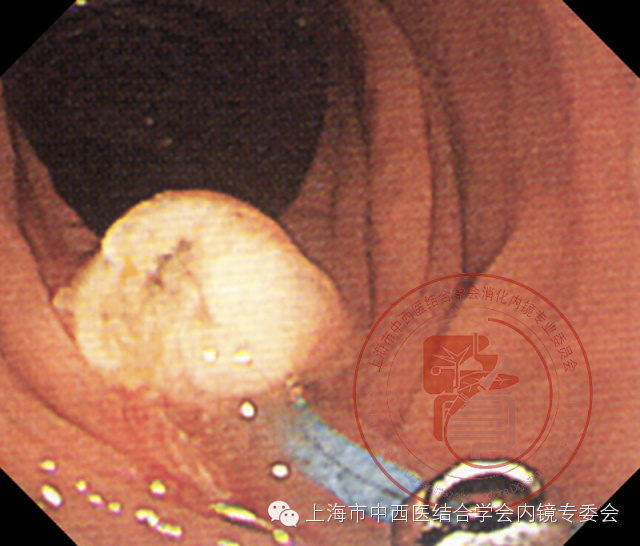

带蒂息肉

切除后创面